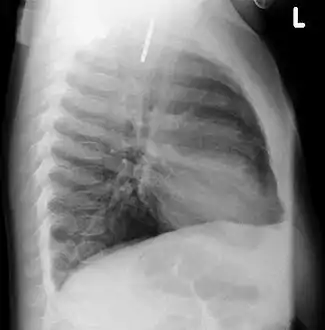

Foreign material in a blood vessel due to an embolization procedure.

Talcosis of the lung due to intravenous drug use. H&E stain.

Foreign bodies can also become lodged in other locations: